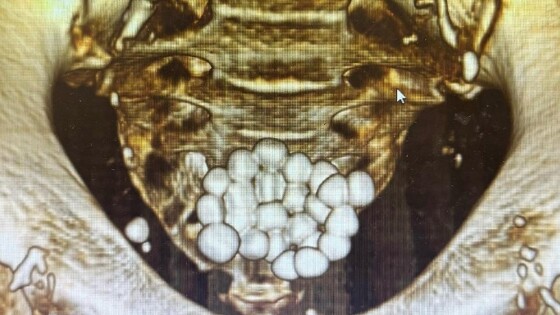

Новороссийске хирурги удалили 24 камня из мочевого пузыря пациента

Врачи горбольницы Новороссийска провели одновременно две лапароскопических операции одному пациенту. Они удалили 24 камня из мочевого пузыря.

На хирургический стол попал мужчина, страдающий аденомой простаты. Из-за осложнений у него образовалось два десятка камней диаметром до 1,5 см. Об этом «Кубань Информ» рассказали в пресс-службе медицинского учреждения.

Операцию провели врачи урологического отделения горбольницы: заведующий урологическим отделением Игорь Довлад и лечащий врач Арслан Темиров. Они одномоментно удалили все камни из мочевого пузыря и провели трансуретральную резекцию простаты.

Операция прошла без разрезов — с помощью современного эндоскопического оборудования. Сейчас пациент чувствует себя хорошо. Через несколько дней его выпишут домой без медицинских трубок. Медики напомнили, о коварстве заболевания, оно протекает безболезненно и проявляется у мужчин старше 45 летнего возраста.